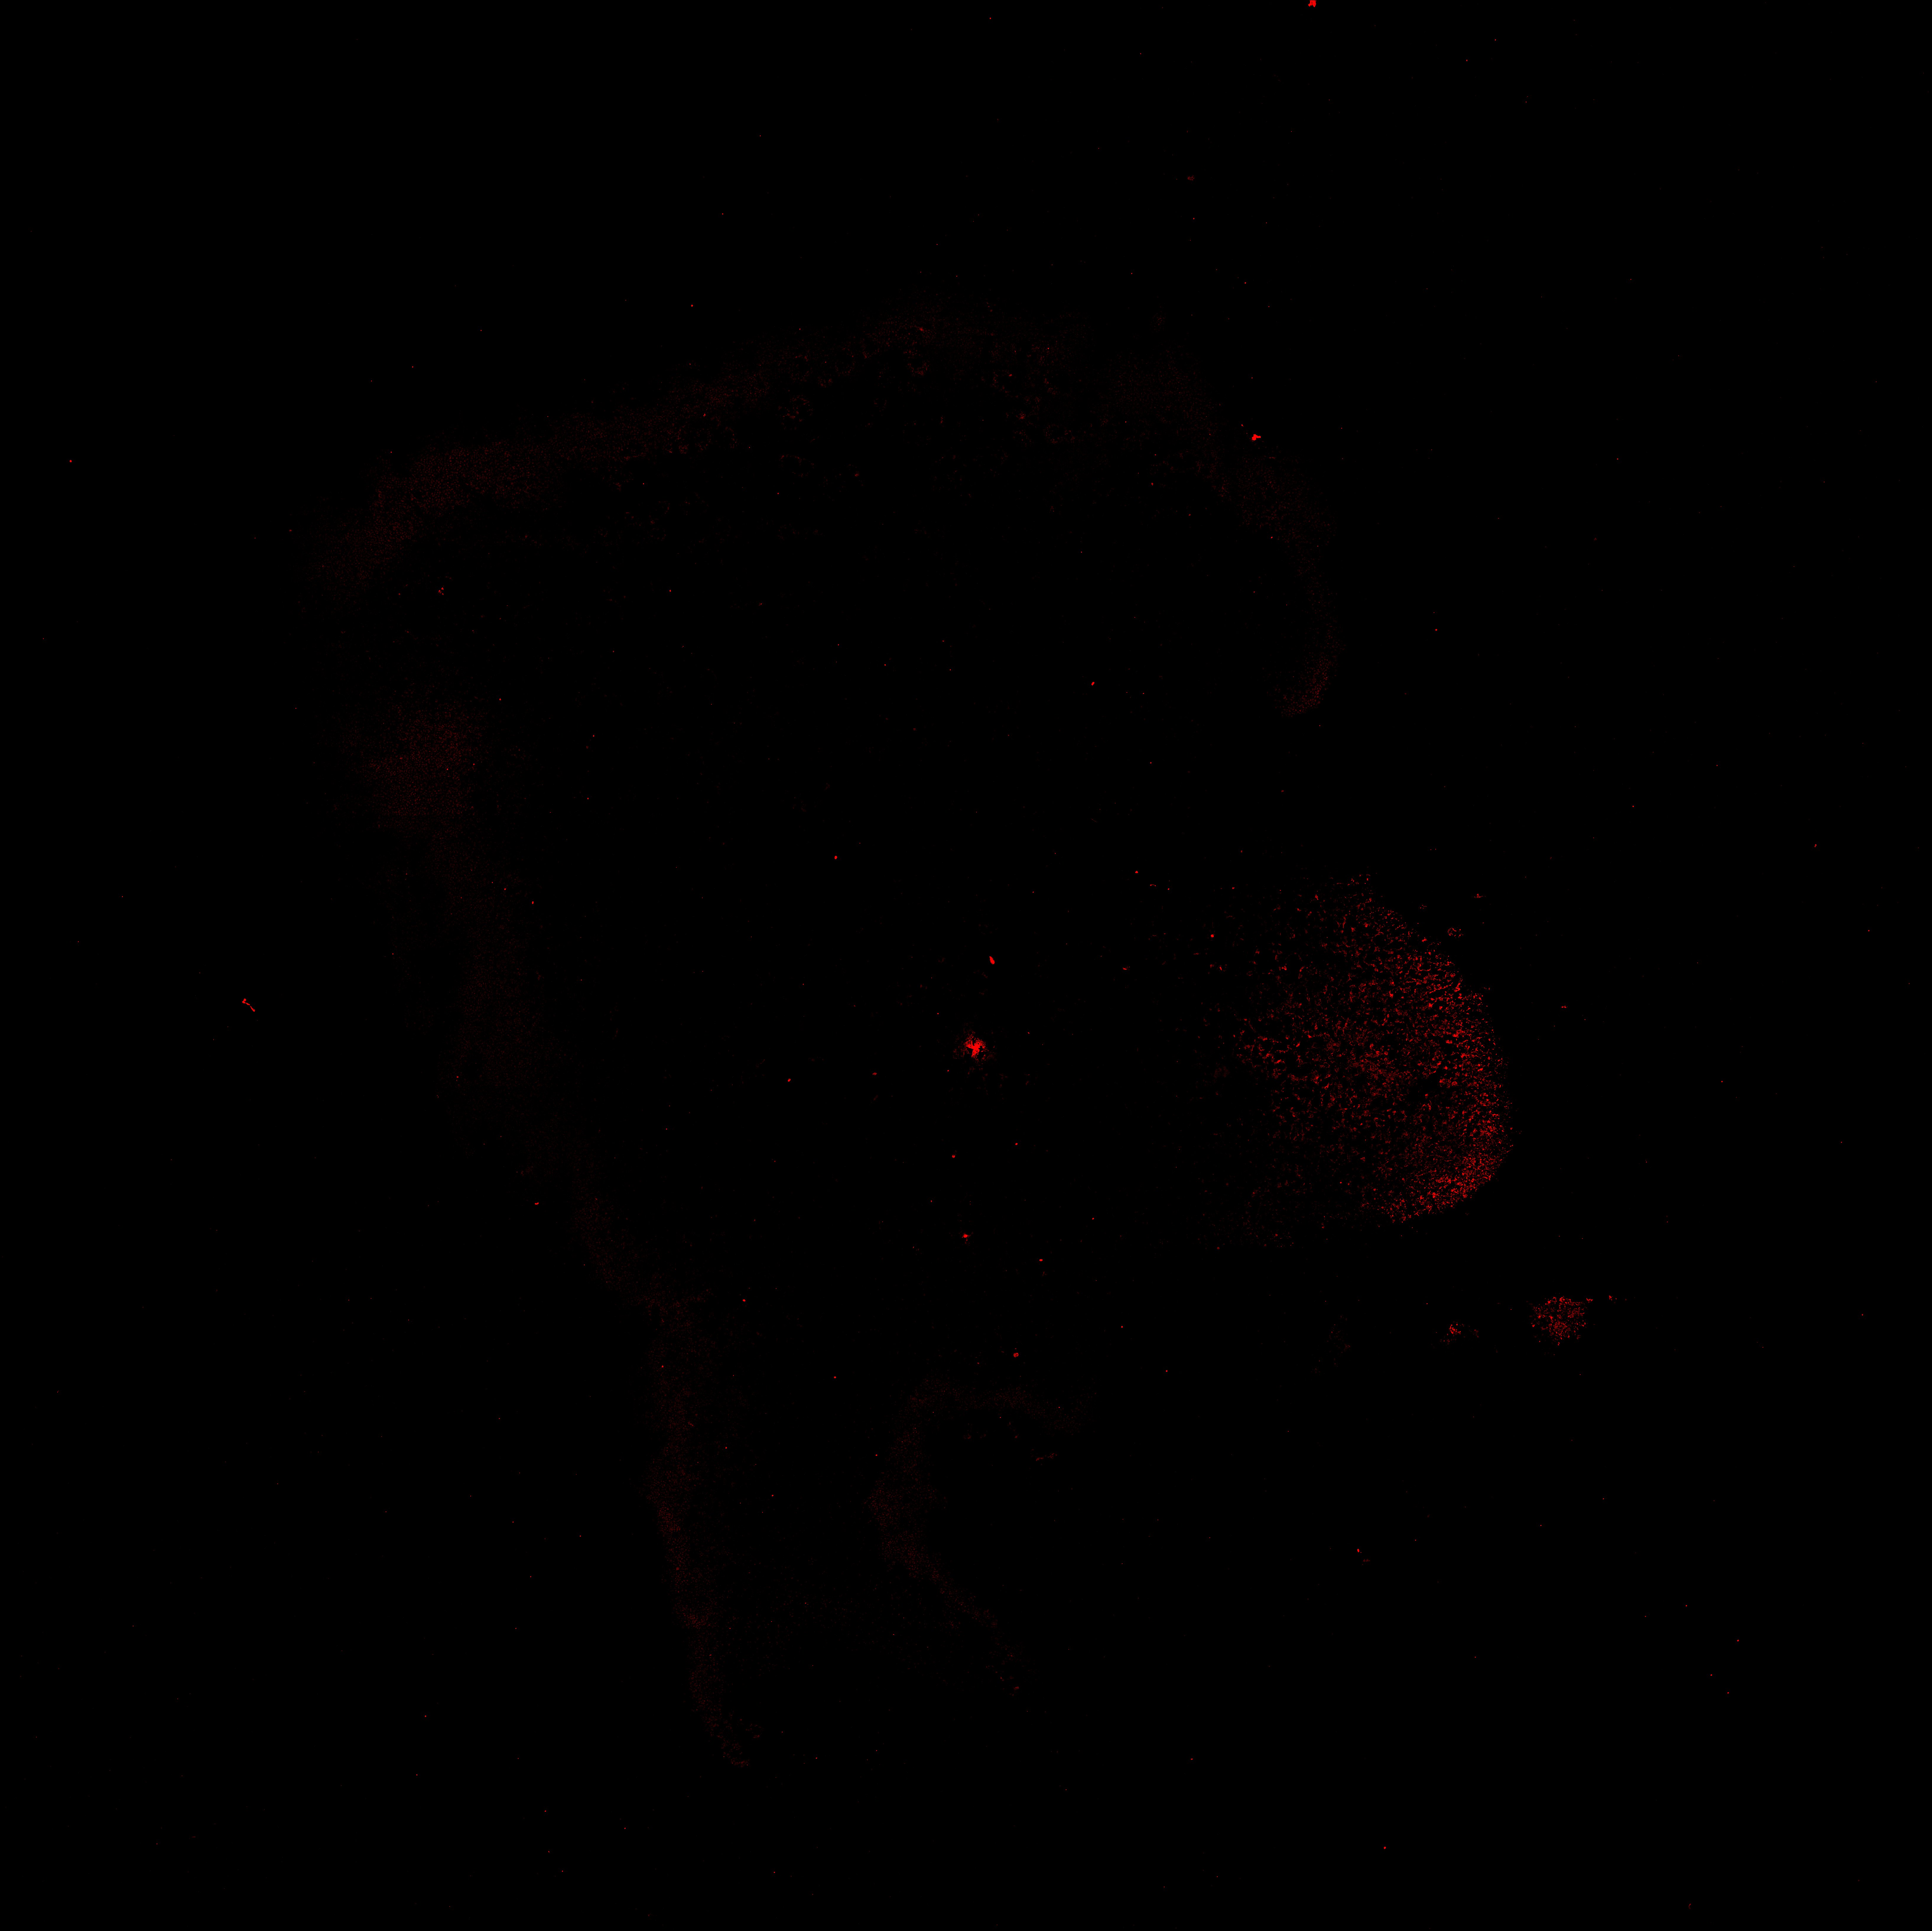

TH

6PCW human midbrain